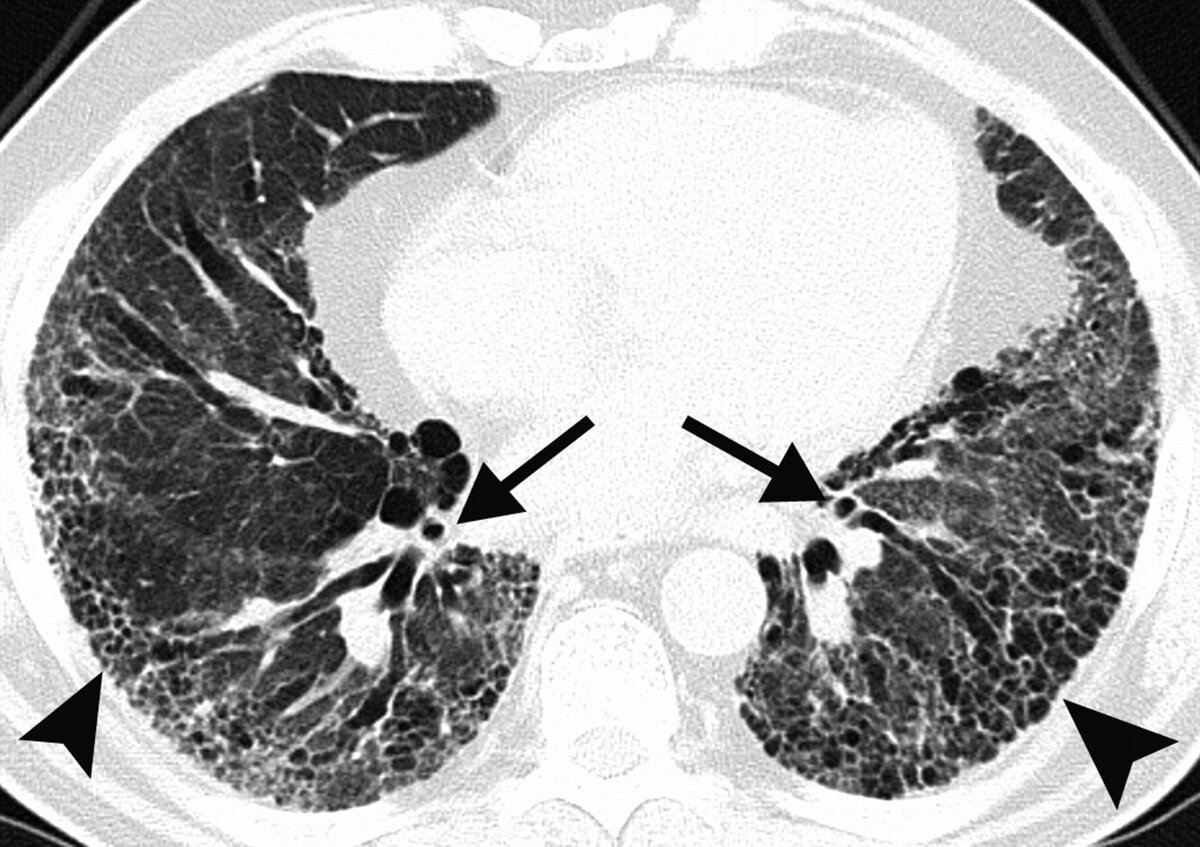

Прежде всего рентгенологи в таких случаях исключает наличие инфильтративных изменений, уплотнений легочной ткани по типу «матового стекла», что характерно для вирусной пневмонии.

Но нередко у пациентов находят фиброзные измененения в каком-то сегменте или сегментах легких, а также плевроапикальные наслоения.

Что касается плевроапикальных наслоений, то они могут выявляться и на обычном рентгене и представляют собой спайки, образующиеся между листками плевры верхушек лёгких.

Считается, что такие наслоения являются следствием перенесенного воспаления. Это может быть пневмония, туберкулёз в анамнезе.

В действительности, случайно обнаруженные подобные спайки на рентгене или КТ лёгких не представляют никакой опасности и не требуют дообследования.

Что же касается фиброзных изменений в легких, то они свидетельствуют о замещении легочной воздушной ткани с формированием соединительной ткани. Это происходит после перенесенных воспалительных или дистрофических заболеваний легких.

Если фиброзная ткань занимает один или пару сегментов легких, то это не влияет на их функцию. При выраженном распространенном или диффузном пневмофиброзе может страдать газообмен и уменьшаться жизненная емкость лёгких, что проявляется у таких больных одышкой и плохой переносимостью физической нагрузки.